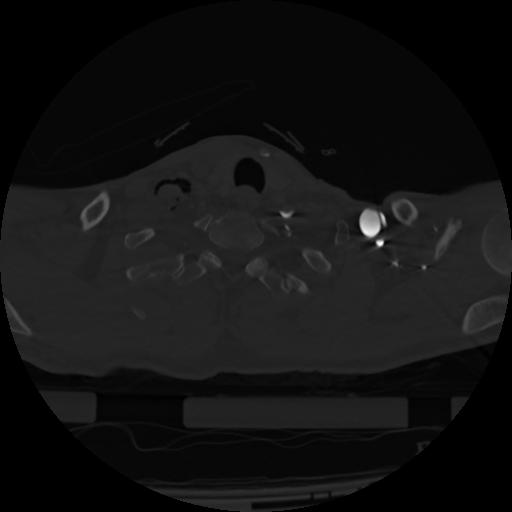

22 ANGIO,CE,Vol,0.5,ANGIO,,